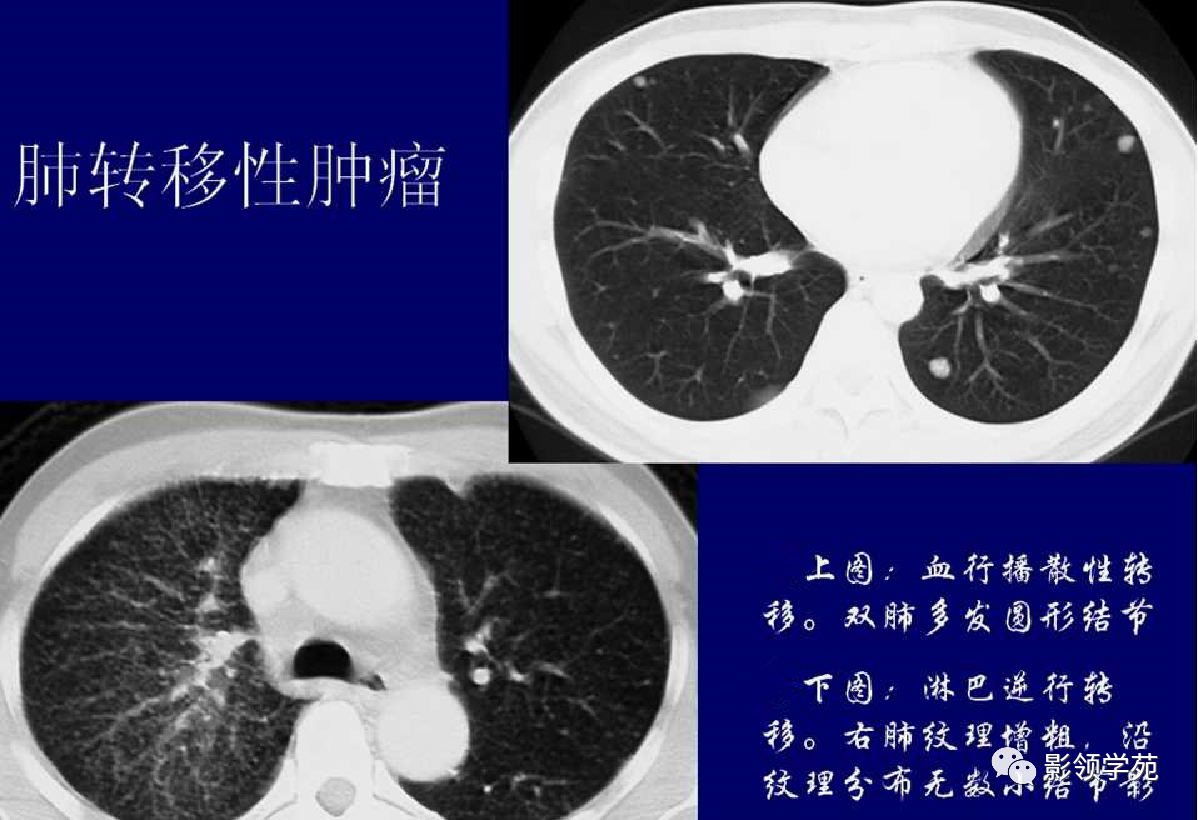

血行转移:双肺多发密度一致、大小形态不一结节状影(下图)

淋巴转移:肺门影增大,自肺门向外部规则索条状影(下图)

1. 血行性转移 :

多发或单发结节,大小不一,边缘较清楚。少数结节伴出血时出现晕轮征,即有略高密度影像环绕结节,使病变边缘模糊。病变有钙化常见于骨肉瘤或软骨肉瘤转移。转移瘤亦可表现为空洞。两肺多发的小结节影具有随机分布的特点,HRCT显示结节位于小叶中心、小叶间隔、支气管血管束及胸膜,结节大小不均匀。

2.淋巴道转移:

HRCT表现为沿淋巴管分布的结节。支气管血管束结节状增粗,并有结节,小叶间隔呈串珠状改变或增粗,小叶中心有结节灶,并有胸膜下结节。病变在两肺弥漫分布或局限于某一部位,以中下肺多见。常合并胸腔积液。约半数病人有纵隔及肺门淋巴结肿大。